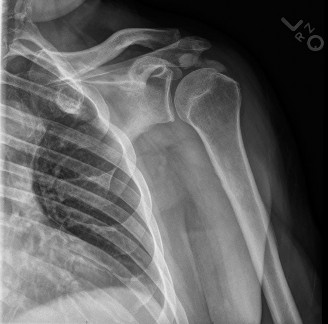

The patient undergoes resection arthroplasty with antibiotic cement spacer and a 6-week course of IV antibiotics. He returns to clinic 4 months later with improved pain, CRP <3, however, on examination he has a positive belly press sign and increased external rotation compared with the contralateral shoulder. Imaging is shown in Figure 2–57.

Figure 2–57

The correct answer is (D). The patient has completed his course of antibiotics and his spacer and is now an appropriate candidate for explanation of the cement spacer with revision shoulder arthroplasty, therefore Choices A and C are incorrect. The patient’s clinical examination findings point to rotator cuff tear (specifically subscapularis) which has occurred in the interval between his obtaining his initial total shoulder arthroplasty and his current examination. Therefore, total shoulder arthroplasty (Choice B) is contraindicated, and the patient should have a reverse total shoulder arthroplasty. Objectives: Did you learn...? Recognize the clinical presentation of a patient with infection after total shoulder arthroplasty?